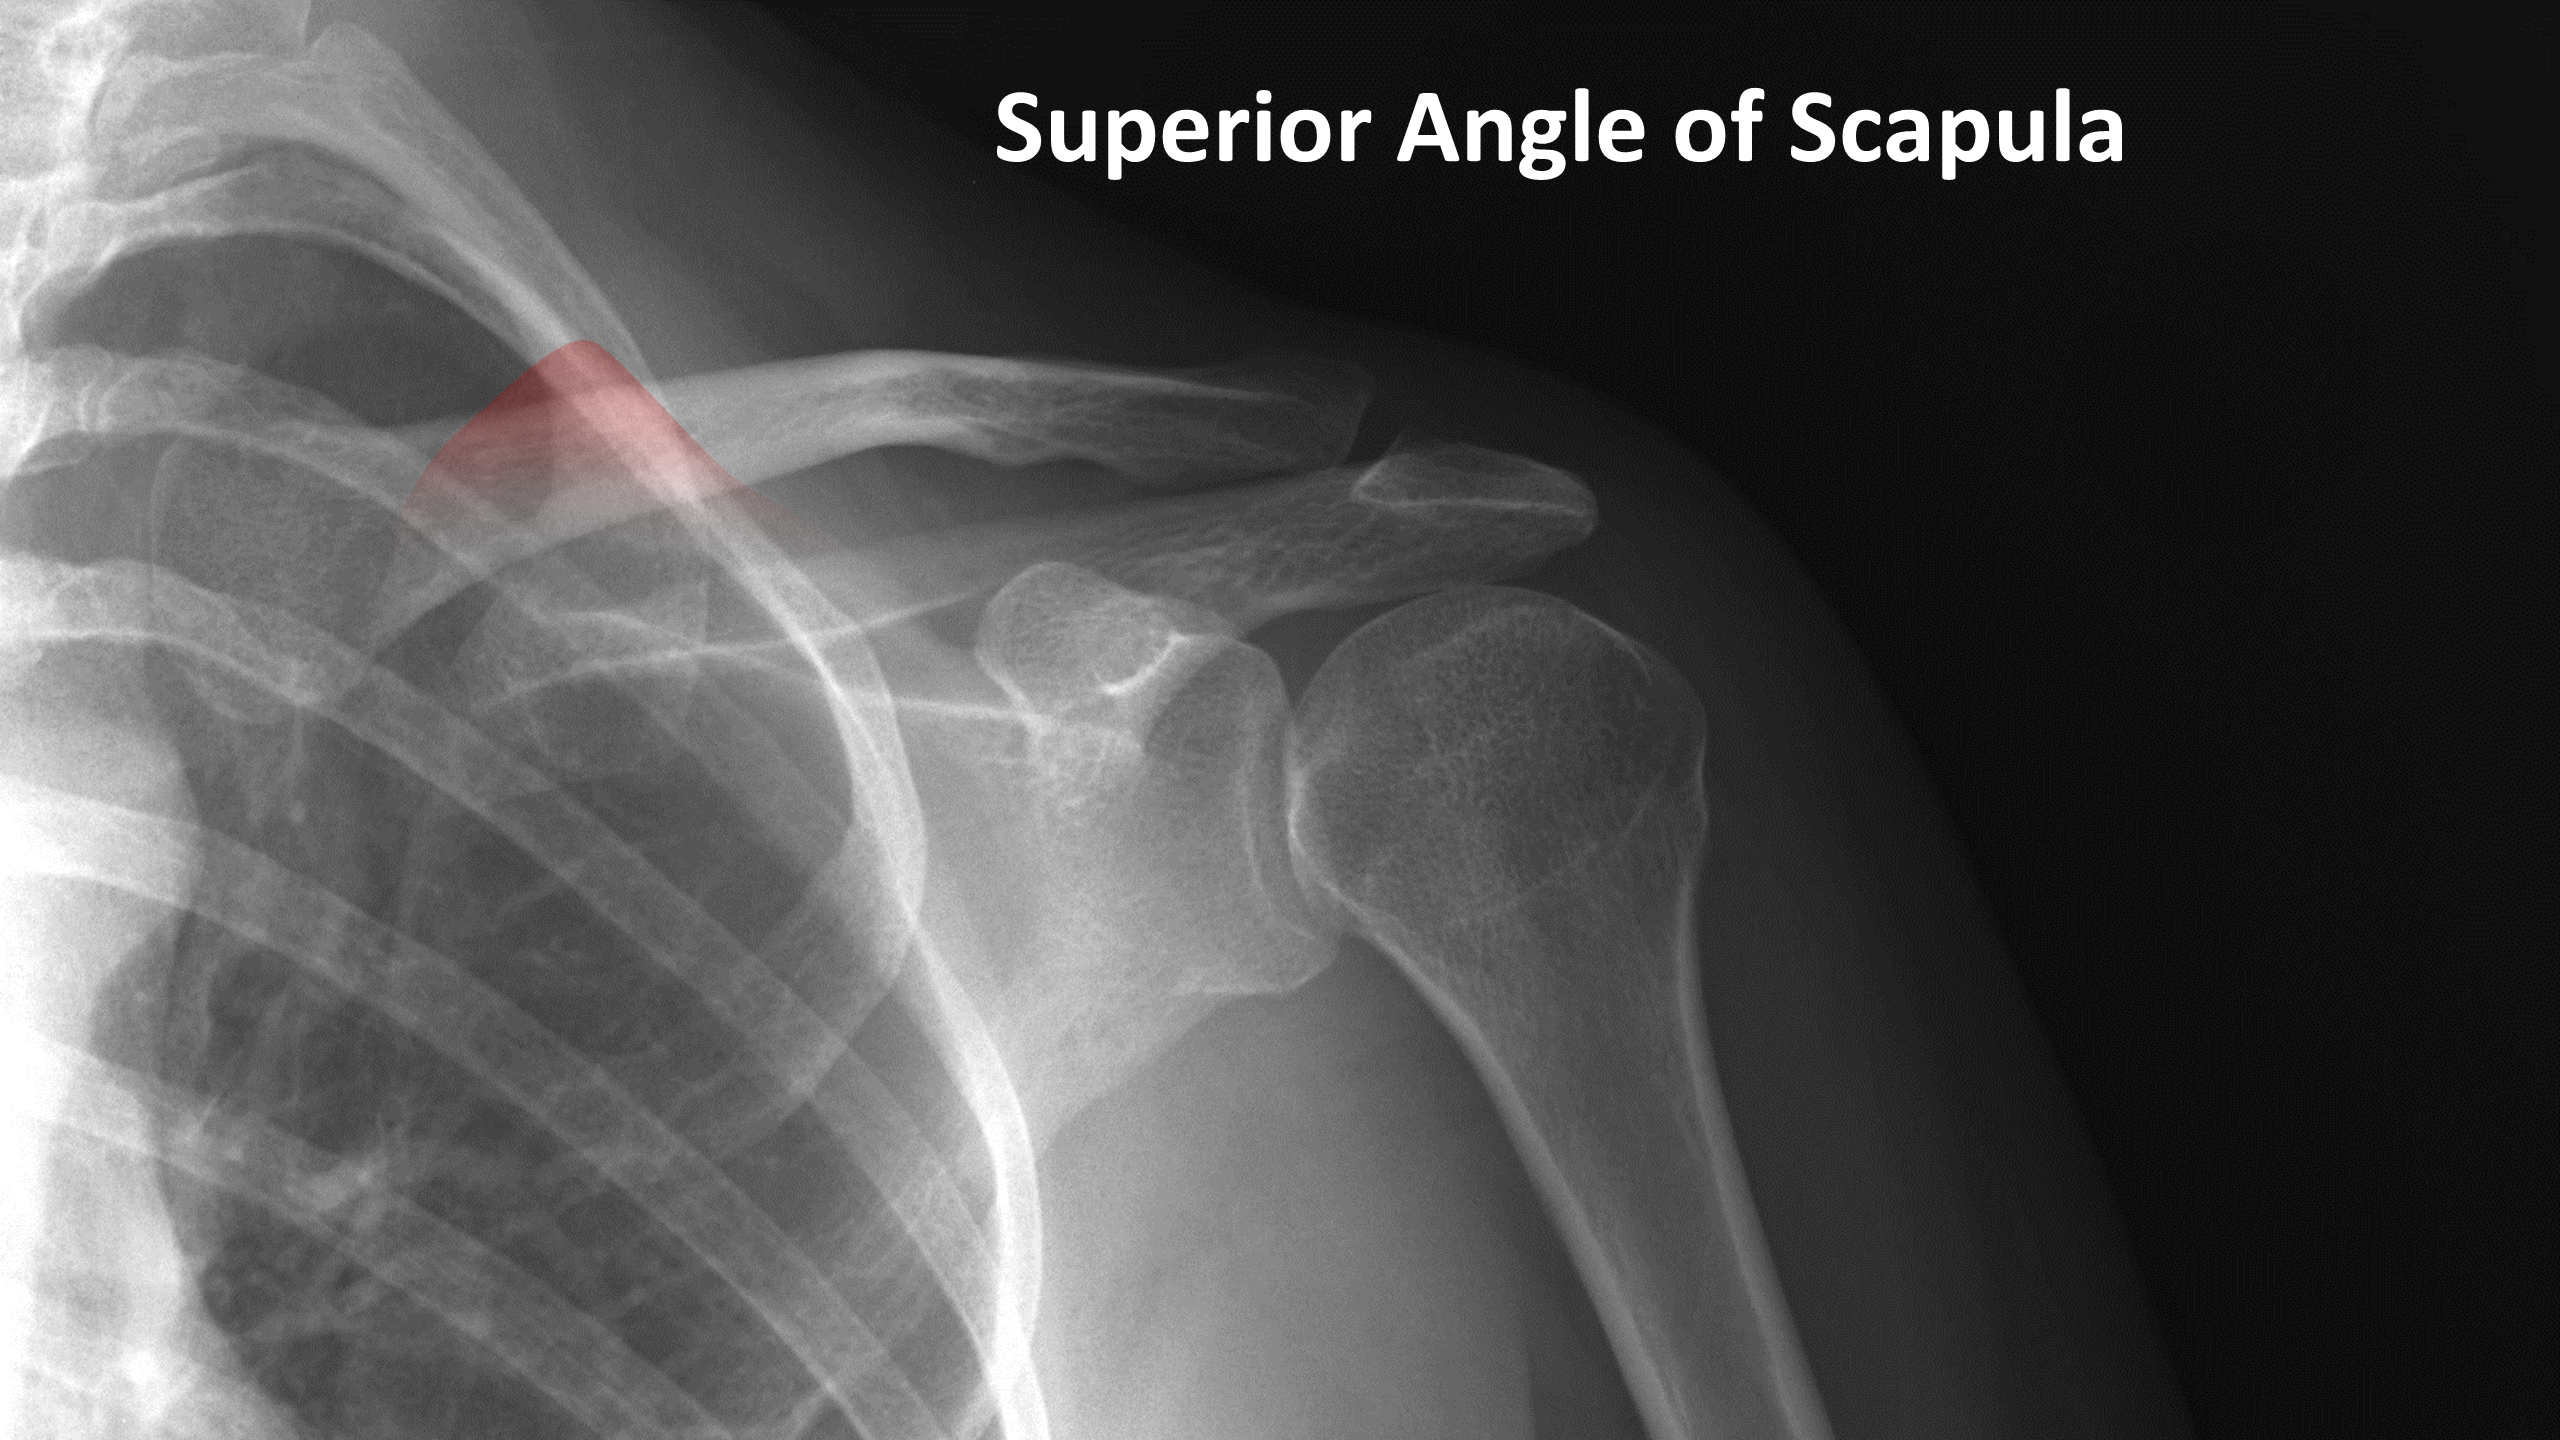

Рентген плеча: примеры снимков и их расшифровка